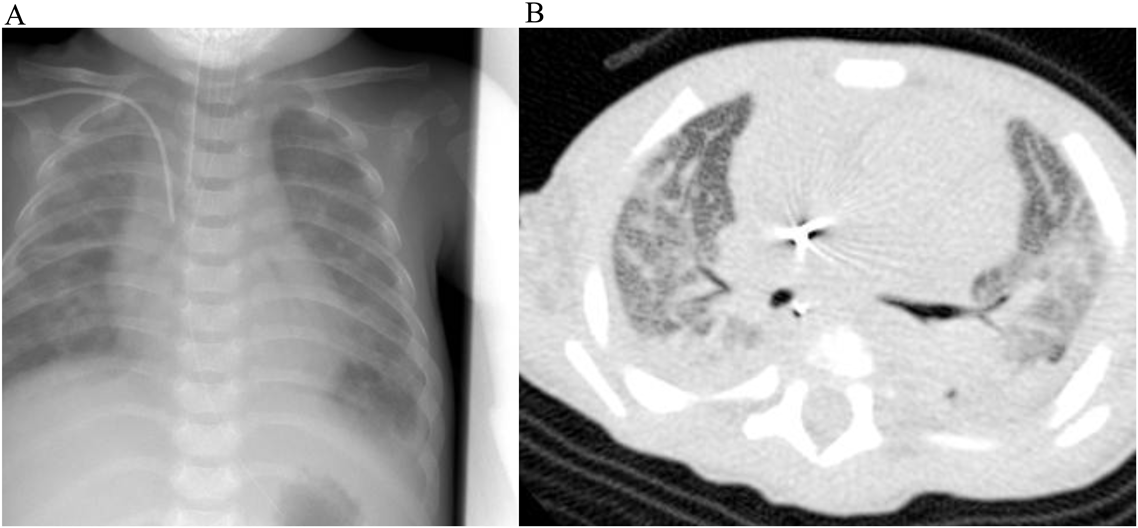

Fig. 2 Chest X-ray and CT scan of the thorax

Chest X-ray shows diffuse alveolar opacities (A). CT scan of the thorax shows diffuse ground-glass opacities, interlober septal thickening and atelectasis (B).

失神の原因は肺高血圧クライシスと考えた.呼吸不全に対し人工呼吸管理とし,ドパミン,ドブタミン,オルプリノンを開始した.しかし入院当日の夜間に肺高血圧クライシスが再燃したため,筋弛緩薬も併用し深鎮静とした.入院2日目に肺高血圧の状況を把握するため,心臓カテーテル検査を行った.FiO2 0.8の条件で肺体血圧比1.3,平均肺動脈圧43 mmHg,肺動脈楔入圧6 mmHg,肺血管抵抗10.3 unit·m2であった(Table 1).同日よりエポプロステノール2.0 ng/kg/minで持続投与を始め,一酸化窒素ガス(nitoric oxide: NO)吸入も併用した.その後エポプロステノールを2週間で10.9 ng/kg/minまで漸増した.エポプロステノールの増量に合わせてNOは漸減中止した.入院1週間でPDAは自然閉鎖したが,肺高血圧は持続していたため,特発性肺動脈性肺高血圧(idiopathic PAH: IPAH)と初期診断した.入院2週間経過した頃よりエポプロステノールの増量に伴い肺水腫が目立ち始めた(Fig. 2A).肺水腫の増悪があるたびに,水分制限および利尿剤の増量,エポプロステノールの減量を行った.

ところが,入院3か月時(生後5か月)に急激な肺水腫を来たし,酸素化係数(PaO2/FiO2: P/F ratio)140へ低下,胸部CTで両肺野に粒状影とびまん性のすりガラス様陰影,小葉間隔壁の肥厚を認めた(Fig. 2B).水分制限,肺血管拡張薬の減量,利尿剤増量による除水を行い呼吸状態は改善した.繰り返す肺水腫からPVODを強く疑い,右側開胸で肺生検を行ったところ,肺小動脈は中等度の中膜肥厚と内膜の線維性肥厚を伴う血管が散見されHeath–Edwards分類3度であった(Fig. 3A).肺小静脈は一部の血管で内膜および中膜が肥厚していたが大部分の血管は正常であった(Fig. 3B).IPAHと判断される病理像であり,肺生検結果はPVODを疑う臨床経過と乖離していた.内科的管理のみでは救命困難に至ると予想されたため,入院5か月(生後7か月)に肺移植実施施設へ移植登録を相談したが,体格が小さく,肺移植に適合しないと判断された.入院6か月(生後8か月)にもP/F ratio 130まで低下する重度の肺水腫を起こし増悪寛解を繰り返した.長期間の人工呼吸管理となったため,入院7か月に気管切開を行い,一時的に換気条件は改善した.入院8か月の心臓カテーテル検査では,FiO2 0.4の条件下で肺体血圧比0.40,平均肺動脈圧24 mmHg,肺血管抵抗2.1unit·m2と肺動脈圧の改善を認めた(Table 1).肺水腫の頻度も減少し,循環動態は比較的安定して経過した.この頃遺伝子検査を行ったが,BMPR-2(bone morphologenic protein receptor-2),ALK-1(activin like kinase-1),ENG(endoglin)いずれも変異は検出されなかった.入院11か月(1歳0か月)頃より心臓超音波検査で右心房・右心室の拡大が徐々に進行して肺高血圧が悪化し,また血液検査上もNT-pro BNPが3,000台まで増悪した.入院12か月に全身麻酔下でブロビアックカテーテルを留置したが,術後に重度の肺高血圧クライシスを起こし,NO吸入を再開した.右心系拡大はさらに増悪し,NT-pro BNPも12,000台まで悪化した.肺水腫の増悪が懸念されたが,他に改善の可能性のある治療がないことからエポプロステノールを慎重に24.3 ng/kg/minまで漸増した.しかし次第に完全鎮静下でも肺高血圧クライシスを起こすようになり,右心不全の急速な増悪を認め,1歳2か月(入院13か月)で永眠した.